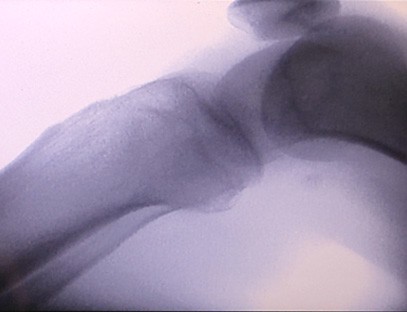

Is táirge ardchaighdeáin é ár Meaisín X-gha Ortaipéideach a dearadh go háirithe le haghaidh íomháithe ortaipéideacha. Is féidir é a úsáid le haghaidh diagnóis agus pleanáil cóireála ar choinníollacha ortaipéideacha éagsúla, lena n-áirítear bristeacha, dislocations, airtríteas, agus siadaí cnámh. Tá sé feistithe le teicneolaíocht X-gha chun cinn a chuireann ar chumas íomhánna ardcháilíochta le nochtadh radaíochta laghdaithe. Tá córas íomháithe ardtaifigh ag an meaisín agus is féidir íomhánna d'aon struchtúr cnámh a ghabháil le soiléireacht mhór.

Is féidir ár Meaisín X-gha Ortaipéideach a úsáid i speisialtachtaí leighis éagsúla, lena n-áirítear ortaipéidic, néareolaíocht agus leigheas éigeandála. Is minic a úsáidtear é chun breathnú fluarascópach ar chnámha géaga daonna, ospidéil Tréidliachta agus peataí, Cóireáil créachtaithe ag láithreáin spóirt, foirgnimh, longa farraige, limistéir iargúlta agus láithreáin pháirce míleata. I measc cuid de na hiarratais chliniciúla tá:

1. Diagnóis bristeacha, dislocations, agus gortuithe cnámh eile.

4. Pleanáil réamhoibríoch do lialanna ortaipéideacha.